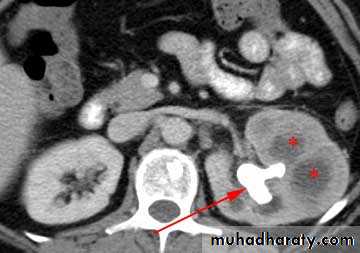

High density renal stonesStage horn calculus KUB filmsradio opaque stones

Bilateral HU + HN